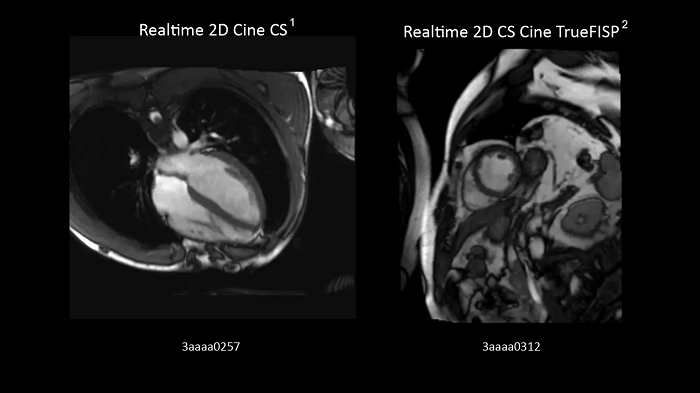

Compressed Sensing Cardiac Cine

Compressed Sensing Cardiac Cine for free-breathing Cardiac Cine imaging.

Left:

- BioMatrix Spine 32

- Body 18

Right:

Realtime 2D Cine CS. Image Credit: Siemens Healthineers

Realtime 2D Cine CS TrueFISP. Image Credit: Blemsersi Radfospital Australian, Germany